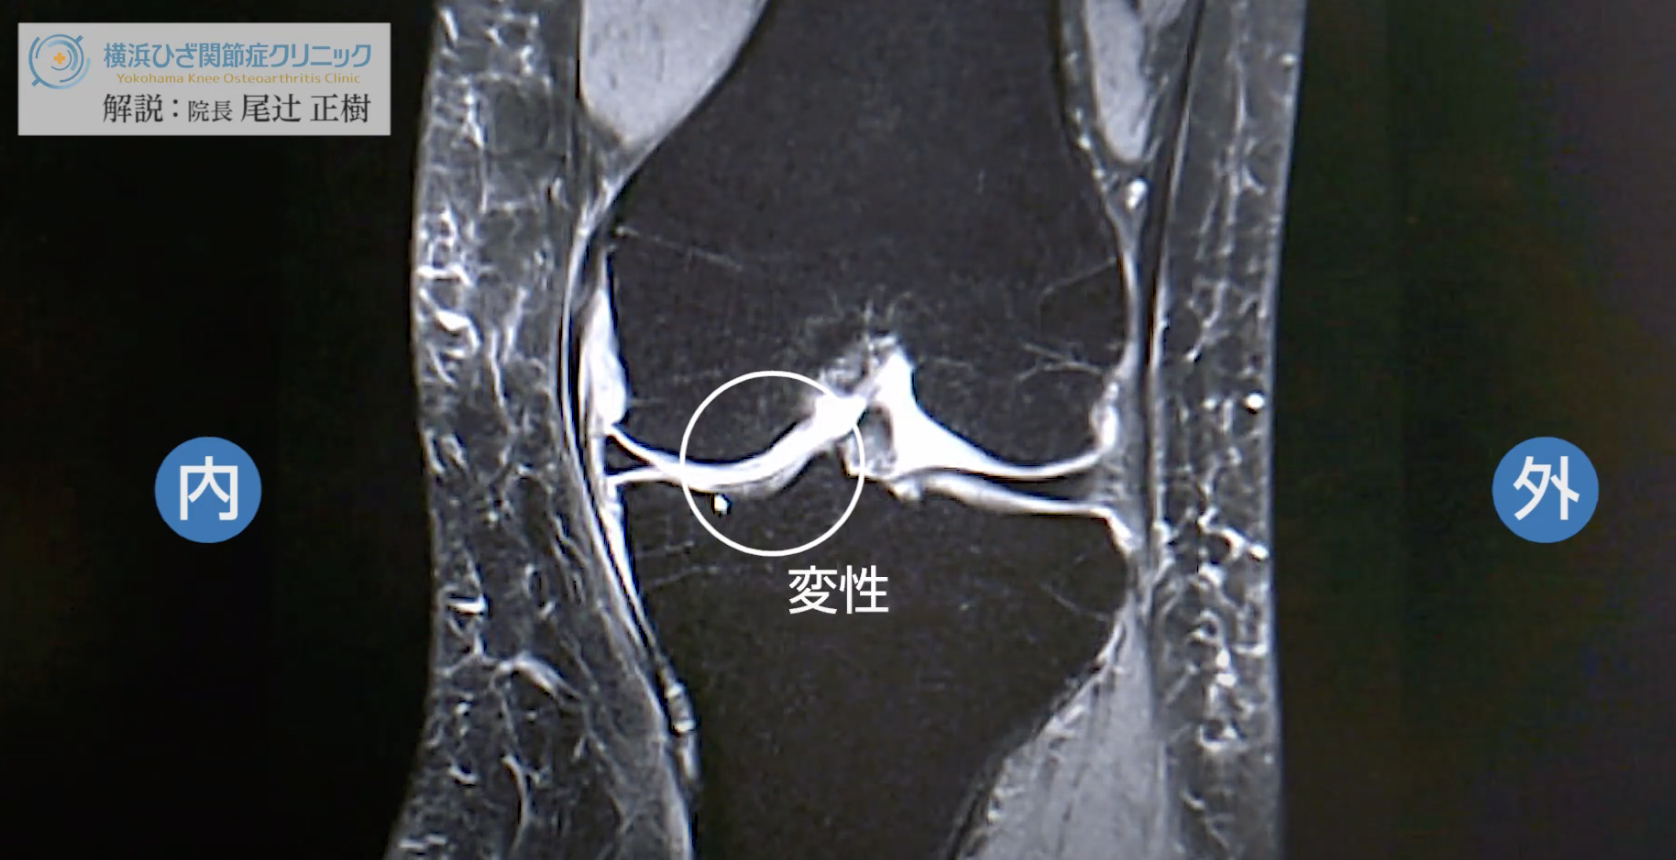

磁気共鳴画像法 (MRI) 検査は、電波と磁場を使用して臓器、組織、その他の構造の画像を取得します。他のスキャンでは必ずしも確認できない関節炎の変化が示される場合があります。

通常、MRI 検査の画像は、超音波や X 線などの他の画像検査よりも詳細です。

骨の健康を専門とする整形外科医は、変形性関節症の診断に MRI を使用することが増えています。医師はこれらの画像を使用して、関節周囲の筋肉や軟骨の断裂を探すこともできます。

変形性関節症に対して MRI が実施されることはあまりありません。しかし、関節内の骨や軟組織を評価するための高精度の画像技術であるため、その使用の人気が高まっています。

MRIで変形性関節症がわかるでしょうか?

MRI では、X 線では必ずしも確認しにくい次のような変形性関節症の指標を特定できます。

ただし、このような MRI の画像化は、変性症状と炎症症状を区別するのに役立ちます。